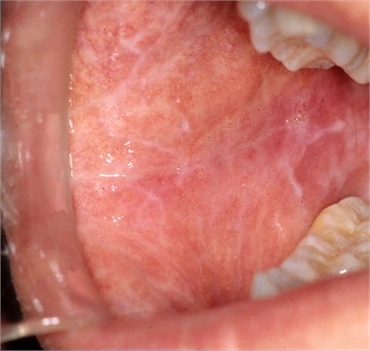

Wickham’s Striae

Wickham's striae is associated with lichen planus irrespective of ethnicity, race and gender. In the oral cavity, Wickham's striae can be seen in the inner linings of the cheek (buccal mucosa), gingiva, lips and tongue. Investigative procedures like dermatoscopy or application of certain oils and stains can help in identification of Wickham's striae. In lichen planus, Wickham's striae are seen on the purplish papules seen in the oral cavity.

It is still unclear at what stage of the development of lichen planus do Wickham's striae form. In his description of the papules of lichen planus, Wickham stated that the affected surface can be divided into two parts. One is a reddish component and the other is a grayish component. The reddish areas lie underneath, over which the grayish layer appears. It is from the grayish area where the lace-like lines originate. The extent of these striae vary in each case. In some cases it is restricted to the papule whereas in some more extensive cases, the whitish lines are present at the length of the buccal mucosa.

The direction of the striae is not fixed either and has been most often described as tree-like configuration. Till date, researchers have established six patterns in which Wickham's striae may present itself. These are circular, reticular (branched), radial linear, globular, perpendicular and veil-like. The presence of Wickham's striae is usually bilateral. This means that it is more often present on both sides of the mouth.